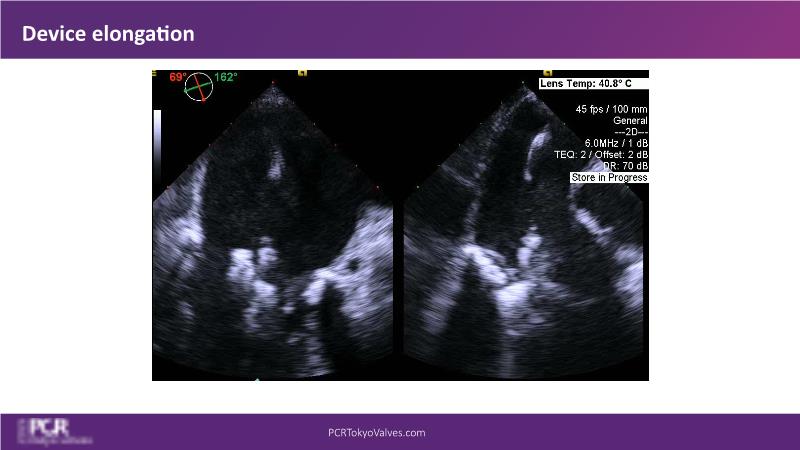

Watch this session to get an overview of a new TEER device, follow the step-by-step procedure related to initial experiences with this device for a Japanese patient with degenerative mitral regurgitation, learn about the latest data from RCT and registries, and follow discussions of challenging TEER cases!

- To learn procedural step-by-step of novel device